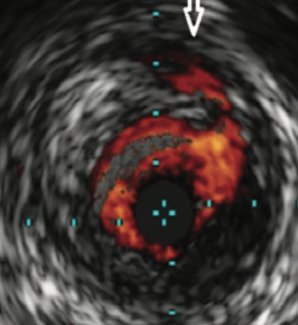

Intravascular ultrasound (IVUS) is an imaging device that provides a 3-dimensional view of what we normally see as a 2-dimensional vascular structure. The device goes over a wire into the vessel, and allows us to see the characteristics...